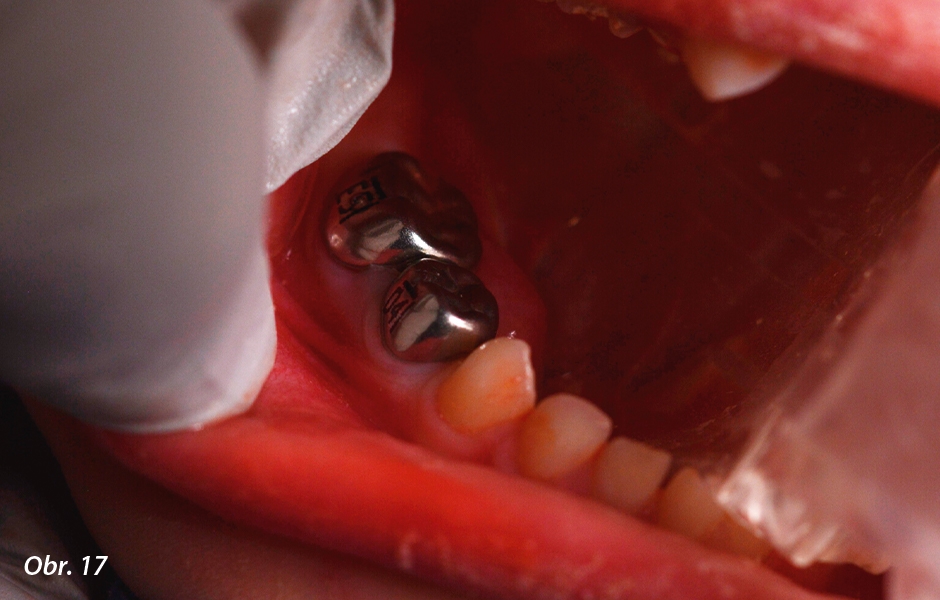

Pulpotomie u distálních zubů: Definitivní náhrada

5letý pacient se dostavil se závažnými ranými dětskými kazy. Pacient k nám byl odeslán svým praktickým zubním lékařem kvůli rozsahu kazů zjištěnému při prvním vyšetření. V té době byl pacient asymptomatický. Kariézní léze se nacházely v zubech 84 a 85. Při radiologickém vyšetření nebyly zjištěny žádné známky furkačních nebo apikálních patologií, u zubu 84 však nebyla dostatečná tloušťka zbývajícího dentinu. U obou zubů byla diagnostikována reverzibilní pulpitida a normální apikální tkáně. Vzhledem k rozsahu nutného ošetření a nespolupráci pacienta byla v rámci plánu managementu ošetření použita celková anestezie. Zuby 84 a 85 byly anestetizovány 4% artikainem HCL s 1 : 100 000 epinefrinu (Septodont) a izolovány pomocí kofferdamu. Po odstranění kazu došlo u zubu 84 k obnažení kariézní dřeně. Pulpotomie byla provedena za použití 6% NaOCl (Vista Dental) a Biodentine™ (Septodont). V tomto případě byla přípravkem Biodentine™ (Septodont) vyplněna celá kavita, aby přípravek fungoval i jako podložka. Oba zuby byly rekonstruovány pomocí kovových korunek (Hu-Friedy).